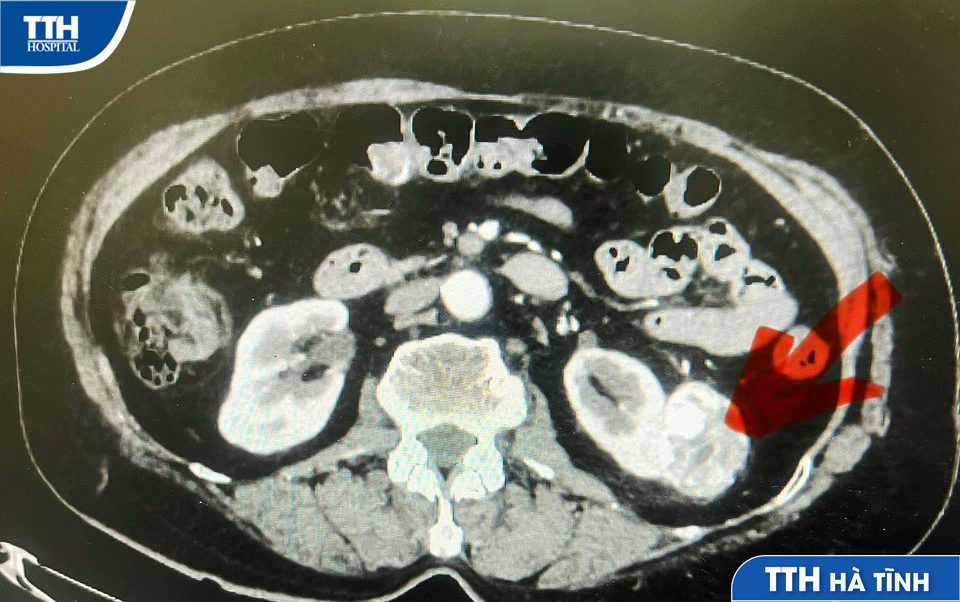

Quá trình khám sức khỏe định kỳ, bà B.T.Đ 74 tuổi trú tại Thị trấn Đức Thọ, Hà Tĩnh được chẩn đoán mắc ung thư thận và được chỉ định phẫu thuật.

Được biết, sức khỏe bà Đ không có triệu chứng gì lạ, không đau, đến Bệnh viện Đa khoa TTH Hà Tĩnh thăm khám tổng quát thì phát hiện khối u thận chưa rõ bản chất, nghi ngờ ung thư.